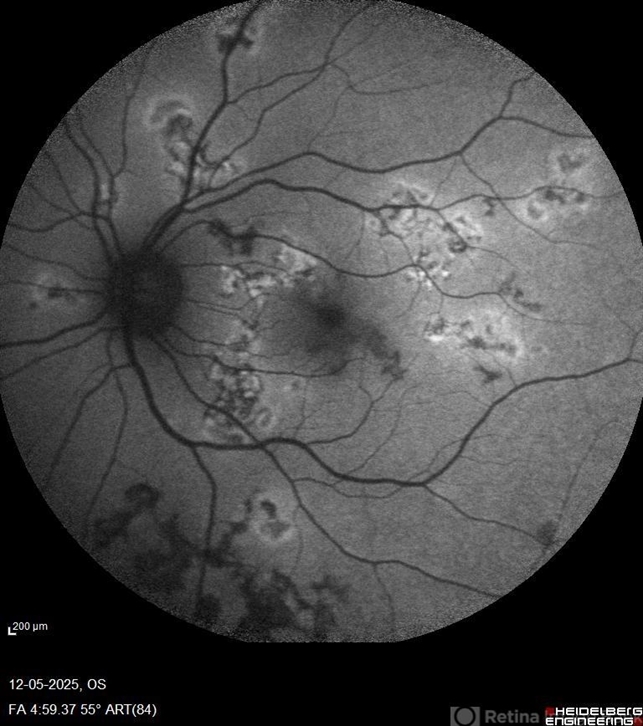

- Auto fluorescence photograph of an 43 year old man with active choroiditic lesion present in the left eye with recurrence